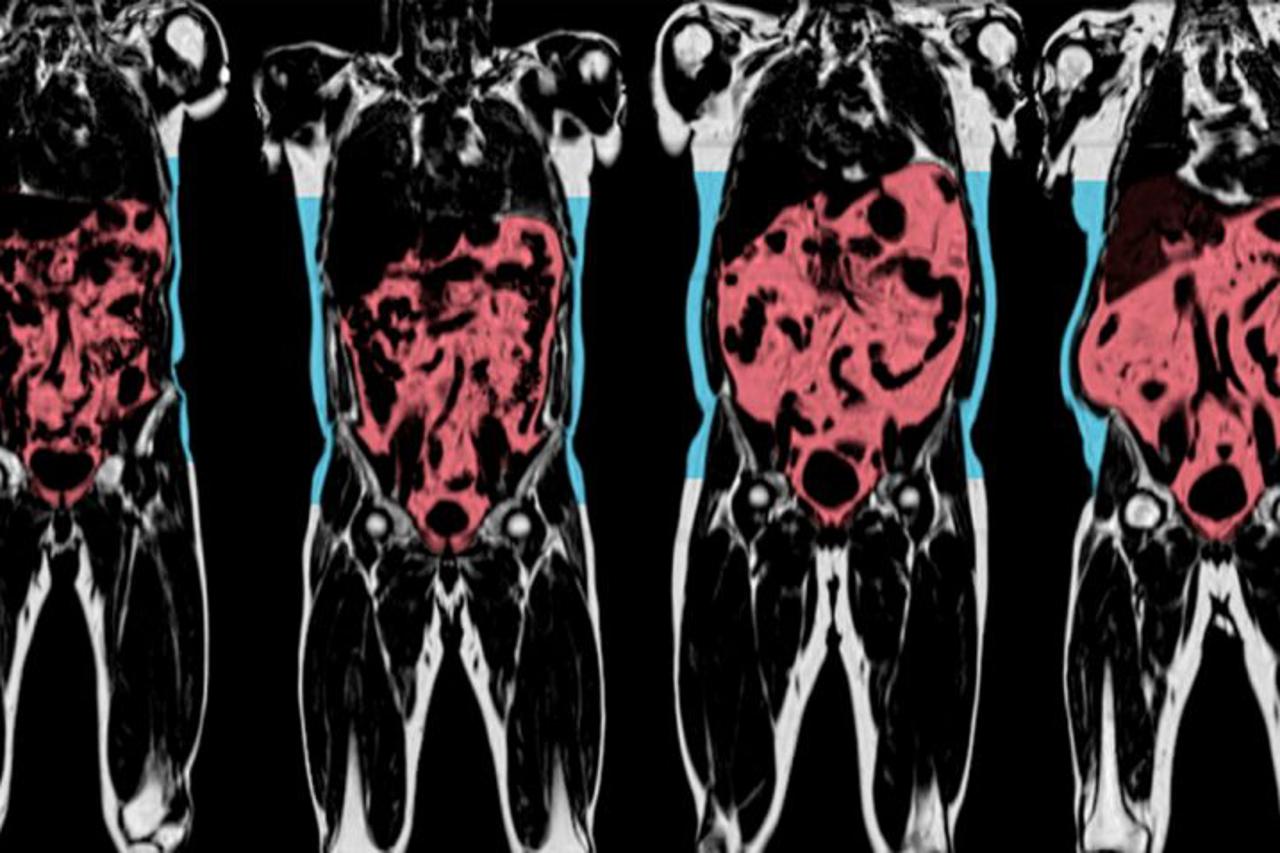

Među visokorizične skupine spadaju osobe starije životne dobi, kao i osobe s dijabetesom, rakom, kroničnom bolešću jetre, bubrega ili pluća, transplantiranim organima ili matičnim stanicama, HIV-om ili drugim imunokompromitirajućim stanjima, poviješću bolesti srca ili moždanog udara, demencijom ili problemima mentalnog zdravlja